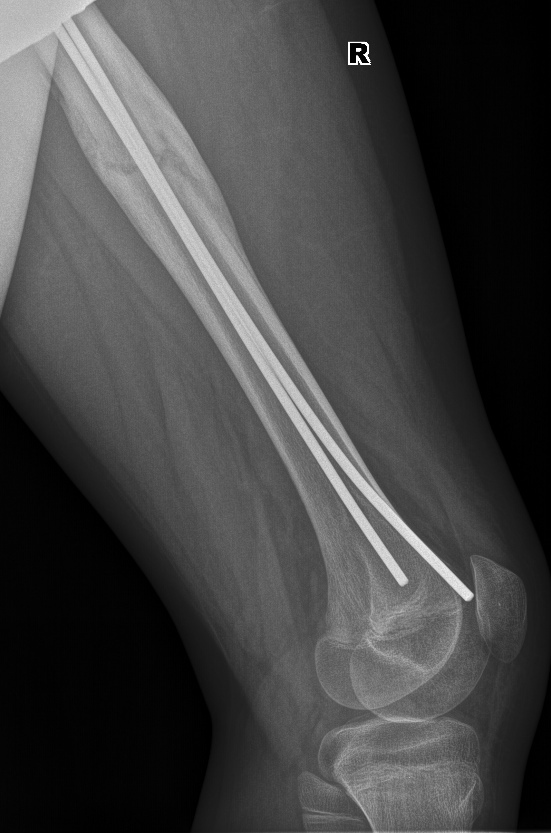

Ребенок 13 лет, перелом бедренной кости. Вставили два тена. Как видно, эндостальная консолидация (сращение внутри кости) слабо выражена, зато резко выраженная периостальная консолидация (костная мозоль вокруг перелома).

И вот еще один снимок с разницей почти в 4 месяца, видно, что срослось хорошо.